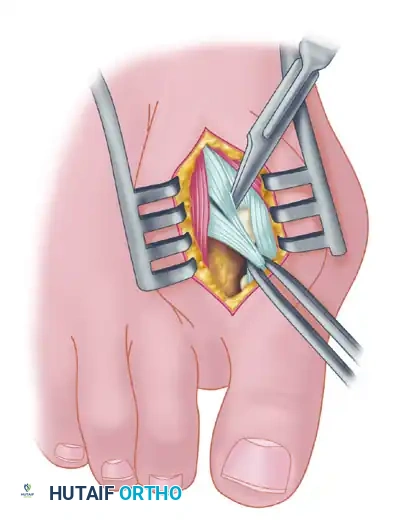

Fibular (Lateral) Sesamoidectomy: Dorsal Approach

In the modern Modified McBride procedure, the fibular sesamoid is rarely excised. However, if a severe, rigid valgus deformity persists after a complete adductor release and lateral capsulotomy, and the sesamoid cannot be mobilized, a fibular sesamoidectomy may be indicated.

- Adequately separate the first and second metatarsal heads using a lamina spreader or Inge retractor.

- Plantarflex the MTP joint 10 to 20 degrees to reduce tension on the sesamoid apparatus.

- Grasp the fibular sesamoid firmly with a small Kocher clamp or sturdy tissue forceps, pulling it laterally into the intermetatarsal space.

- Carefully release the intersesamoid ligament. Once incised, the fibular sesamoid can be delivered into the intermetatarsal space for straightforward removal.

- Surgical Warning: Extreme care must be taken when incising the intersesamoid ligament to avoid severing the flexor hallucis longus (FHL) tendon, which lies immediately plantar to it. If the FHL is inadvertently severed at this level, it generally should not be repaired, as repair often results in a rigid, fixed flexion contracture of the interphalangeal joint, whereas loss of the tendon causes minimal functional impairment.

- Alternative to Excision: Release part or all of the FHB lateral head at its insertion into the fibular sesamoid. Remember, performing both a metatarsal osteotomy and a fibular sesamoidectomy drastically increases the risk of iatrogenic hallux varus.